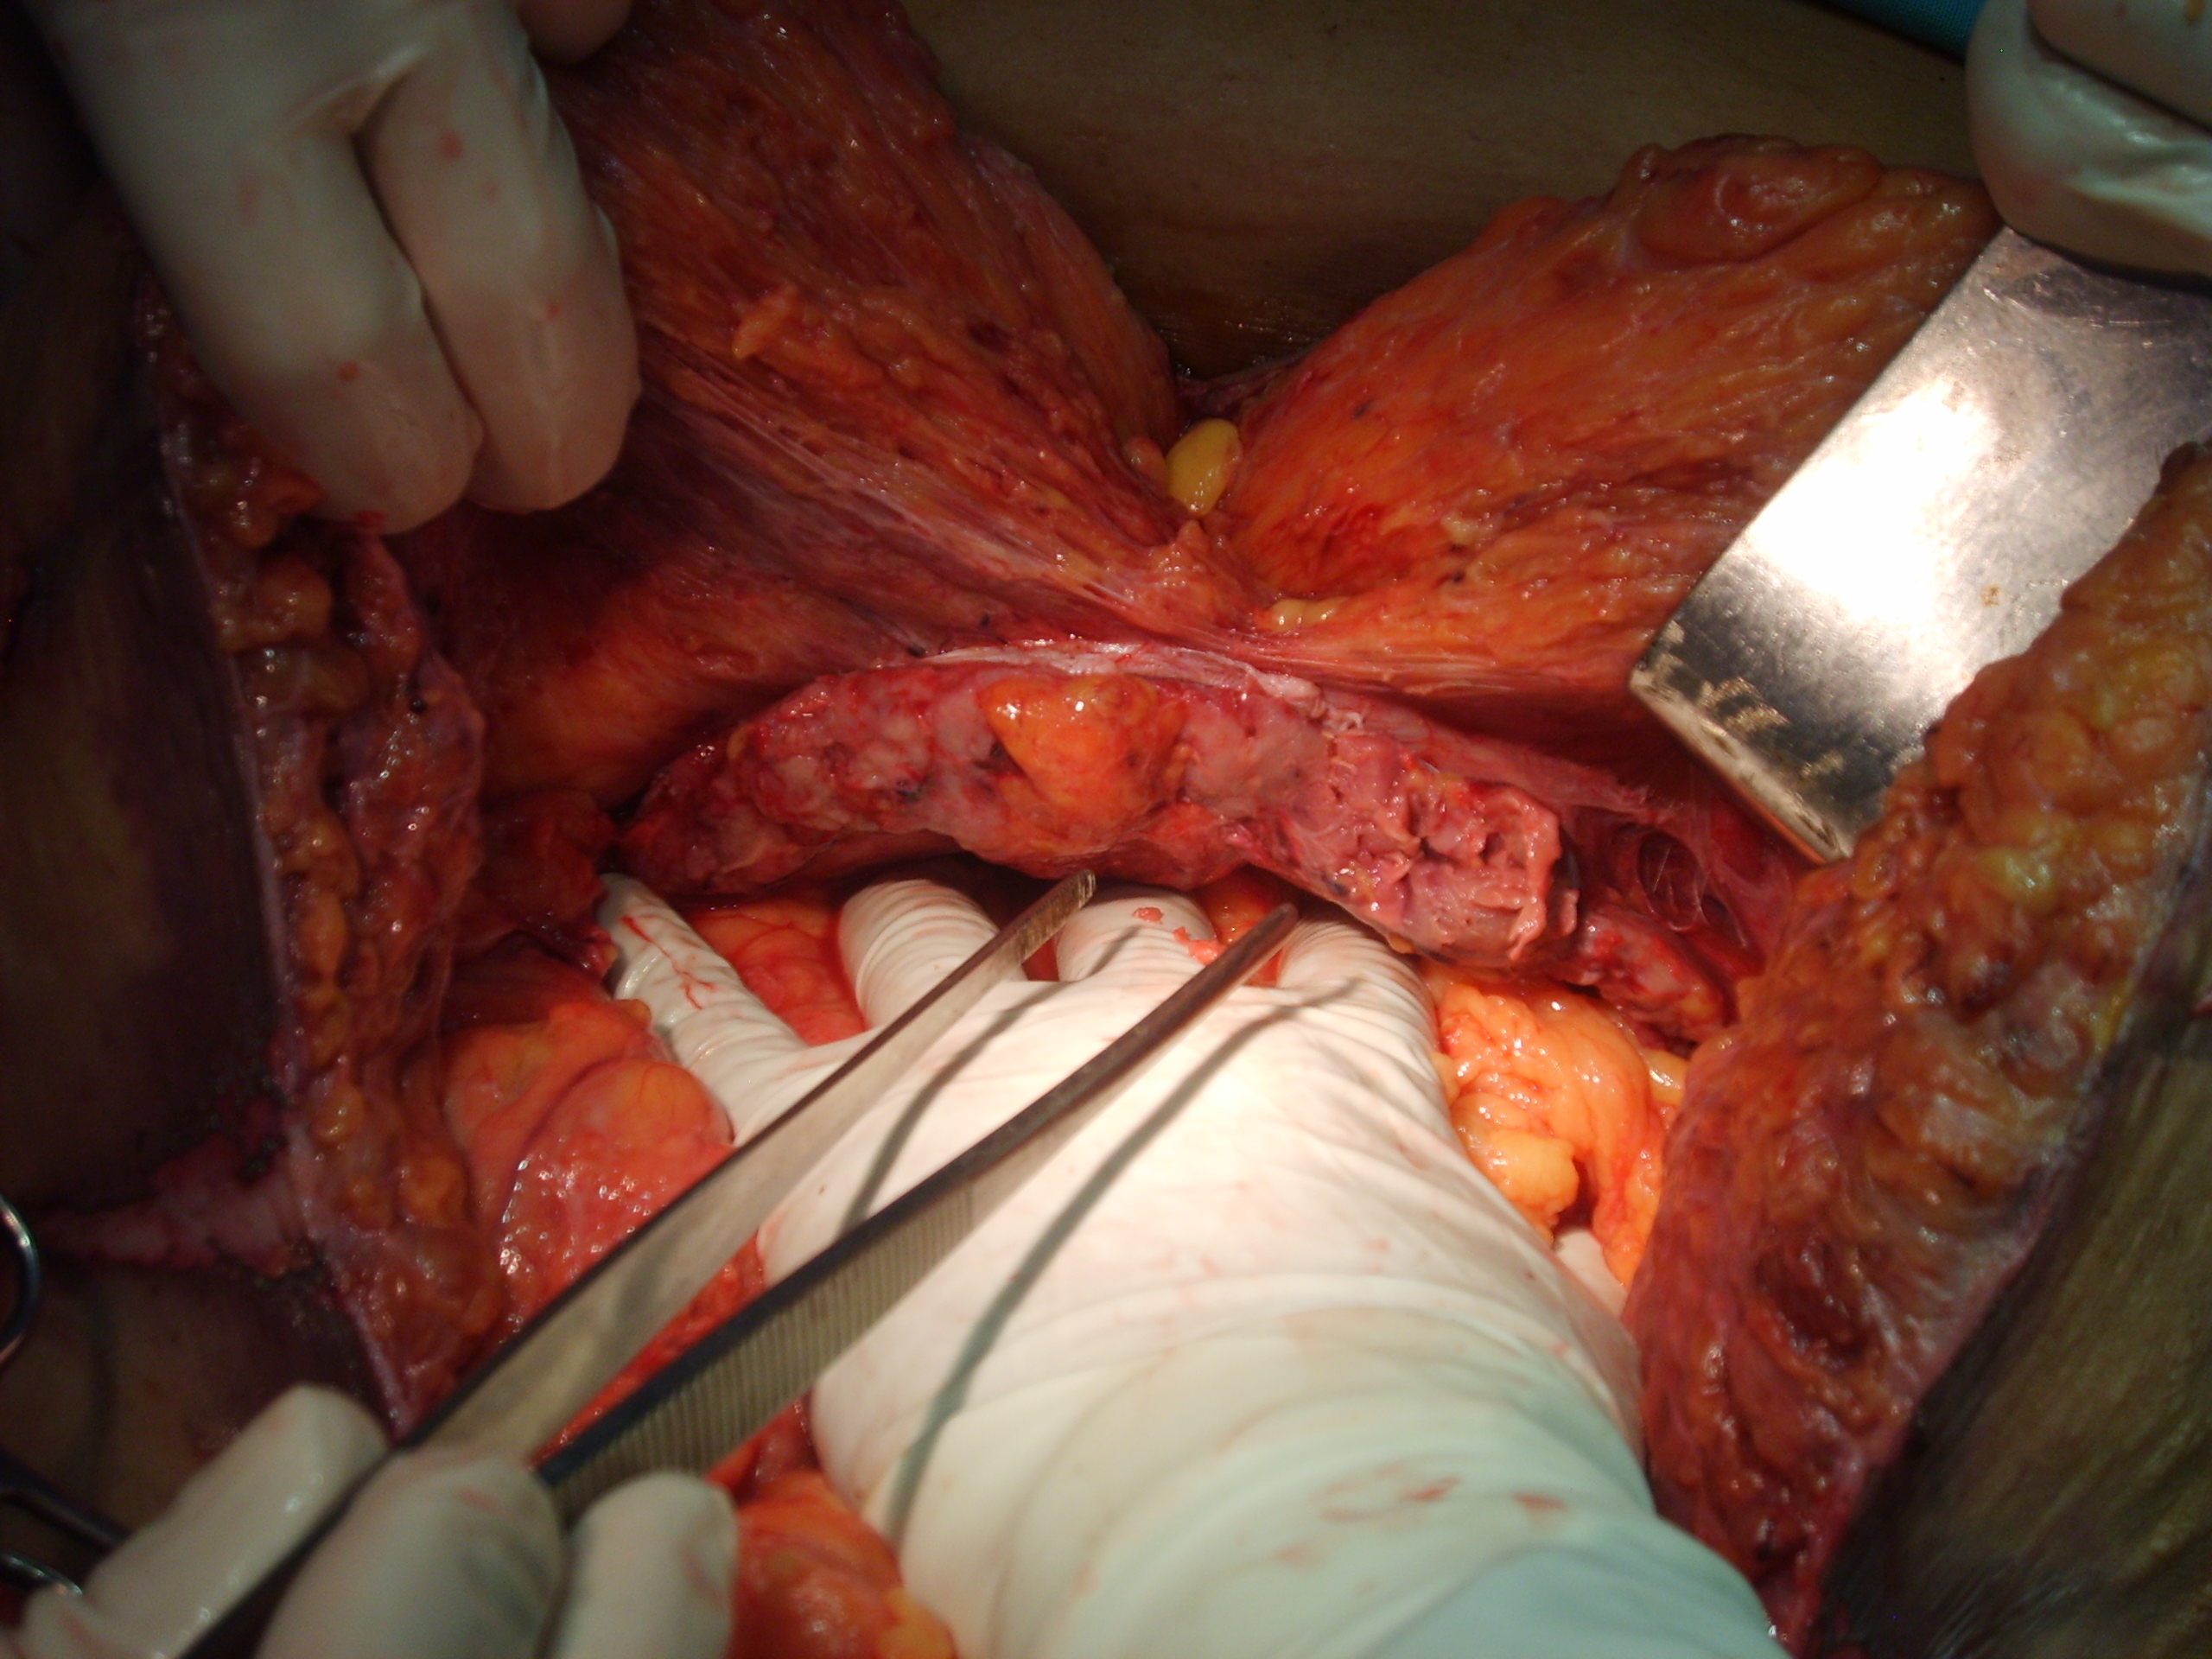

Paciente femenina, 45 años de edad, IMC > 35, (>) ingresa tras sufrir un accidente automovilístico por volcamiento. Sentada en el asiento de atrás con cinturón de seguridad a dos dedos en la cintura. Luego de 14hs del accidente ingresa al servicio de emergencia, lúcida, Glasgow 15, con dolor intenso en miembro inferior izquierdo y tatuaje de cinturón de seguridad a nivel de pelvis. Se realiza TAC de emergencia y se somete a una laparoscopia diagnóstica por descenso del Hto en 5 puntos. Se reconvierte a una laparotomía media , se sutura el mesosigma desgarrado y una laceración del sigma. Se constata hernia traumática con sección completa de pared anterolateral del abdomen. Se deja Abdomen abierto y contenido.

Luego de estabilizada la paciente y al cuarto día de la cirugía del abdomen abierto se lleva la paciente al quirófano. Se constata abdomen con escaso liquido serohemático y asas intestinales sin compromiso vascular por lo que se decide cerrar el abdomen. Es dificultosa la tarea de contener las asas intestinales en la cavidad abdominal debido a la ausencia de pared lateral. Se decide el decolamiento del colon derecho e izquierdo a fin de lograr un espacio para colocar la prótesis, es decir generar un espacio real con el peritoneo para introducir la malla. La sugerencia adecuada del Dr Zorraquino es imposible de realizar, la enferma presenta una retracción importante de los músculos rectos que determinan una cavidad abdominal que supera ampliamente los 900 cm². Se coloca dos mallas de proceed 30 x 30 intraperitoneal fijadas con puntos al espesos total de los remanentes musculares y sobre la misma una malla de prolene 30 x 30 fijada abajo al pubis y a ambas crestas ilíacas y por arriba al plano aponeurótico de los rectos y Oblicuo mayor. Se deja piel y celular abierto. Vuelve a Cuidados Intensivos.

Interesantísimo caso el que nos presenta el Dr. Carlos Cano, bien iconografíado. Se ve en la última foto o así lo interpreto la sección de los músculos rectos y oblicuos.